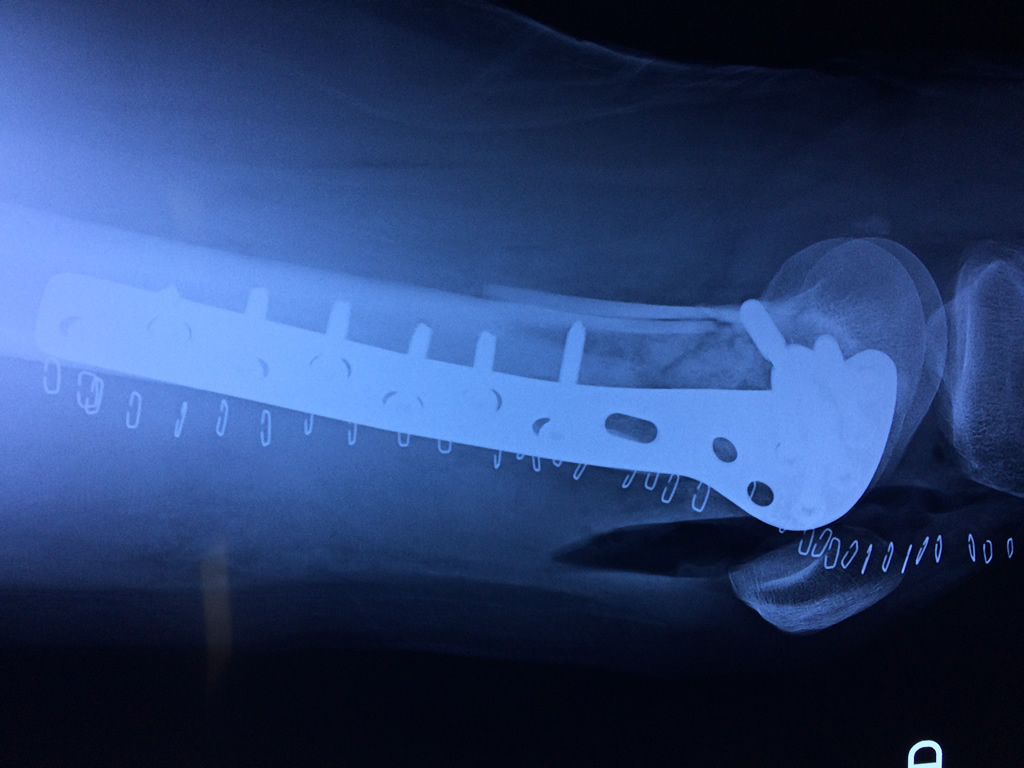

Cirugías de Húmero - Fémur

El fémur es el hueso del muslo, el segundo segmento del miembro inferior. Es el hueso más largo, fuerte y voluminoso del cuerpo humano.